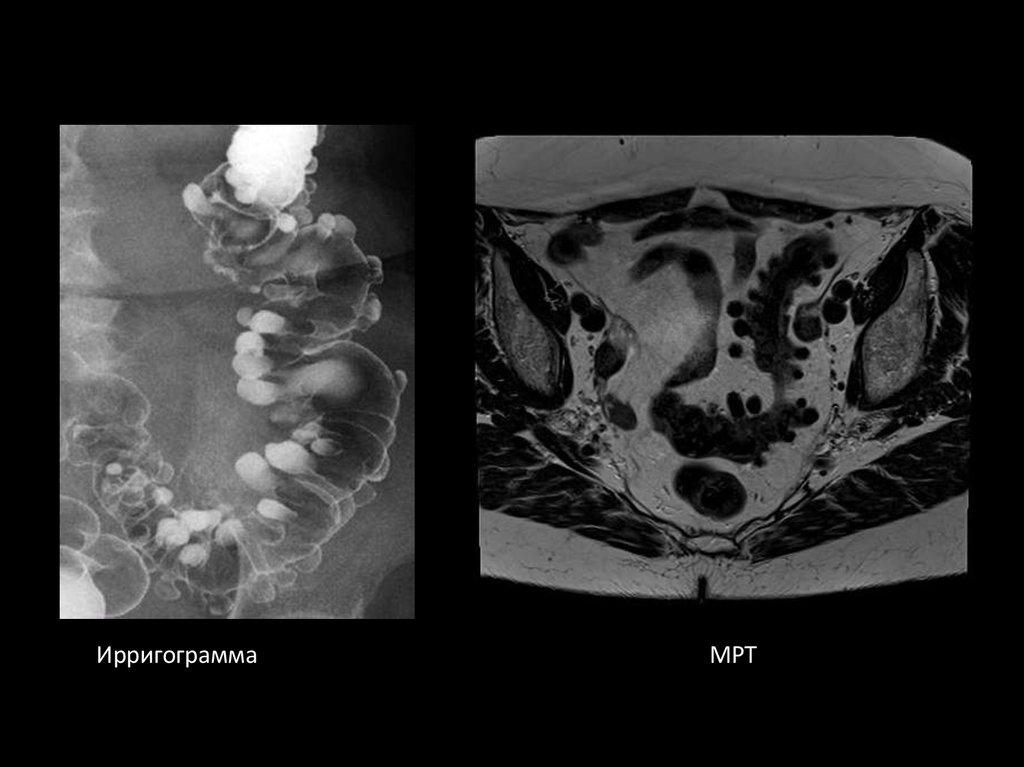

77.

Ирригограмма

МРТ